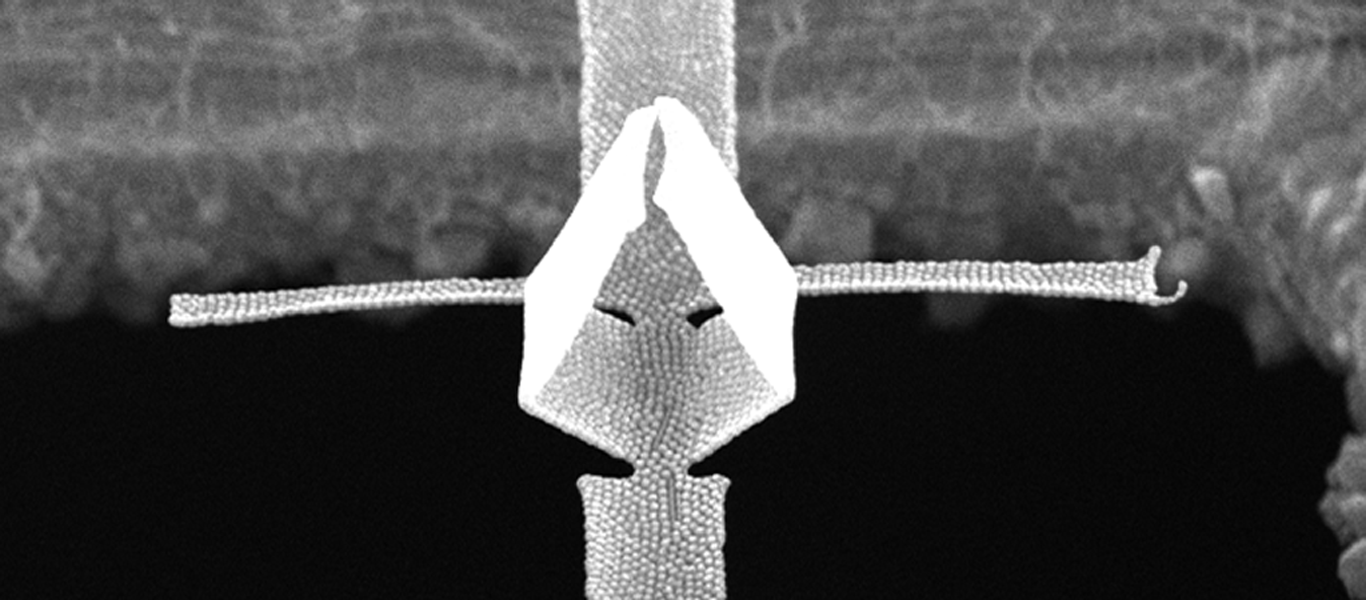

Safer surgeries with microbots

Microrobots are making minimally invasive, vascular surgery even less invasive and risky. Researchers at MCN have developed a 240 micron diameter micromotor capable of navigating through arteries deep inside the human body.